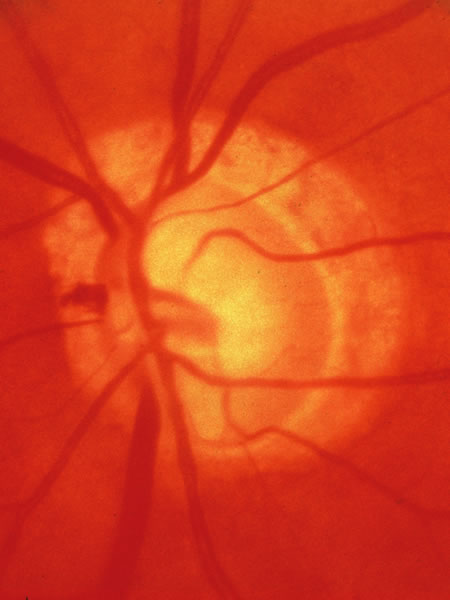

In the retinal nerve fiber layer, axons converge from every direction toward the optic disc and turn to enter the optic nerve through an opening in the outer retina, the choroid, and the sclera. The features and anatomic variation of the normal optic nerve head, or optic disc, are illustrated in Figures 2, 3, 4, 5, 6, 7, 8, 9, 10, 11, 12, 13, 14, 15, and 16. A physiologic excavation (cup) results if the chorioscleral canal is larger than required for the approximately 1 to 1.5 million axons and the supporting glial cells and blood vessels. The size of the excavation depends on how ample is the size of the chorioscleral canal.20,21 In discs where the chorioscleral canal matches the number of axons, the chorioscleral canal itself is typically somewhat taller than it is wide (Figs. 2 and 3). However, because the number of nerve fibers entering the upper and lower poles of the disc is greater than in the temporal and nasal sectors, the boundary of the physiologic cup is more or less circular.22 When the disc is large, it may be nearly circular but the cup likewise nearly circular. However, except in discs of anomalous shape, the width of the rim of neuroretinal tissue is noted in normal, nonglaucomatous optic discs to be greatest in the inferior meridian followed by the superior meridian, and narrowest in the temporal quadrant.23

Fig. 2. Normal optic nerve configuration. Notice that the height (H) of the disc is greater than the width (W). The width of the neuroretinal tissue (A) is also greater in the vertical meridian than in the nasal and temporal meridians (B); thus, the physiologic cup is round.

Fig. 3. Normal disc untilted, taller than it is wide. The neuroretinal tissue in the upper and lower sectors is more abundant in these sectors than others, so the central cup is round. A narrow white line marks the disc boundary and represents the lip of sclera that in humans almost universally separates the choroid from the optic disc tissue around the entire circumference.